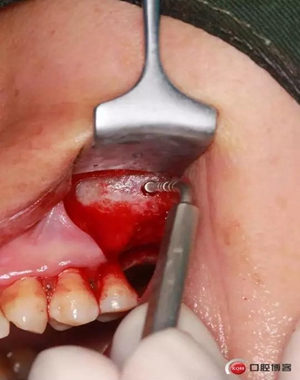

改良式外提升工具盒-外提 科貿(mào)嘉友收錄

六個(gè)月之后